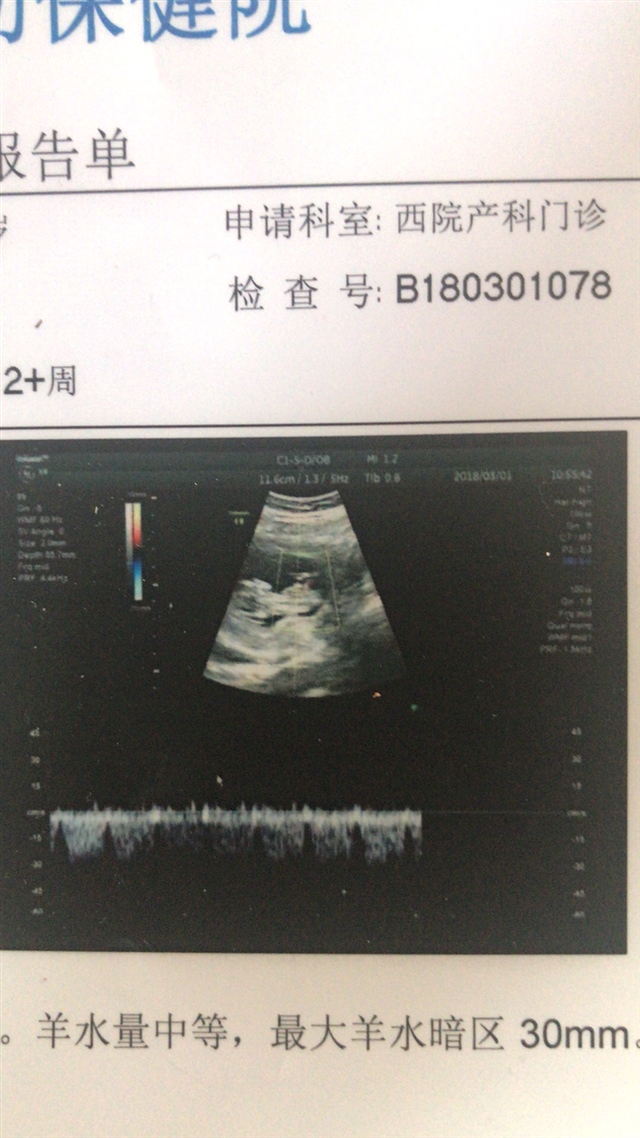

孕22周+2天

看着像男孩

优可卓教育李贞[帖主]:请问你会看B超图吗